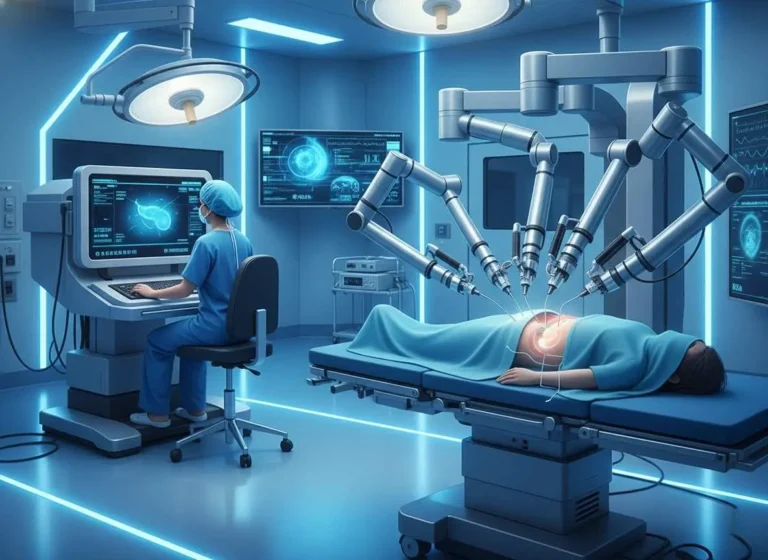

Introduction Minimally Invasive Cancer Surgery in Mira Road. Let’s understand, Cancer treatment has evolved dramatically over the past few decades, with surgical…

Why Choose Laparoscopic Cancer Surgery in Mira Road for Cancer Treatment Cancer treatment has evolved significantly over the past few decades, with…